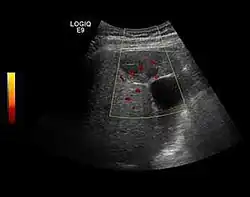

Hydatid liver cyst. Diagnostic criteria are the presence of membranes and sediment inside.